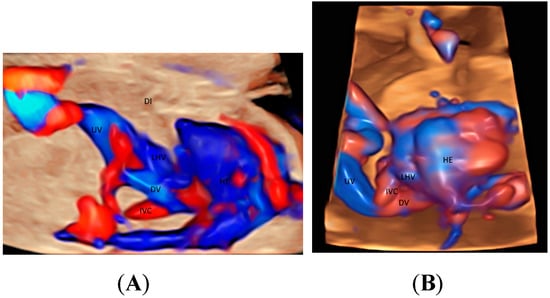

2.4. Abdomen

| Abdomen and other parts | Precordial veins | Umbilical arteries, Renal arteries Splenic artery Hepatic arteries | Small vessels in lung, liver, spleen, kidney, adrenal gland and limbs |

| Abdomen | Precordial veins (HDFI) | GBM TUI | Anomalies of the precoridal venous system Persistent right umbilical vein Abnormal venous returns to the right atrium |